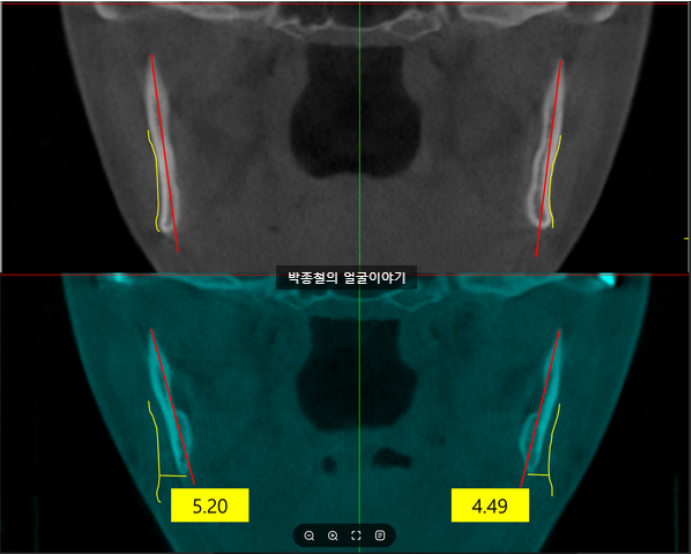

위의 사례처럼 사각턱 수술 없이 양악수술만 받은 환자의 경우, 수술 후 1년 6개월이 지나면서 사각턱 부위가 자연스럽게 줄어들고 얼굴형이 갸름해진 것을 확인할 수 있습니다.

1년 6개월 사이에 사각턱부위에 어떠한 시술을 안했음에도 수술직후에 비하여 사각턱의 수직적인 길이가 줄어 들었습니다.

측면 이미지에서도 사각턱의 수직적 길이가 감소한 것이 확인됩니다

연조직을 기준으로 얼마나 얼굴이 작아졌는지 확인해봅니다.